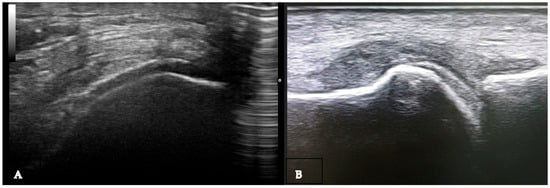

Figure 5.

Erosions (arrow) of the metatarsal head (MT) in a patient with gout. To note a grade 2 urate aggregate at the level of the metatarsophalangeal joint. ET—extensor tendon, P—phalanx.